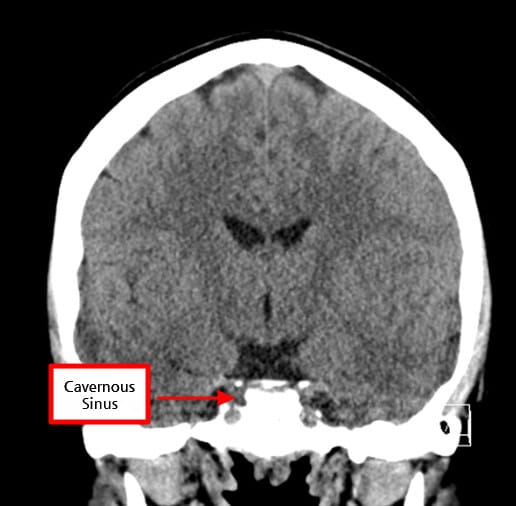

| ✅ 해면정맥굴(Cavernous sinus) 침범 여부 확인 |

| 측방 침범 시 수술 접근과 예후에 영향을 미칩니다. |

Cavernous Sinus

Cavernous sinus는 접형골(sphenoid bone) 옆쪽에 위치한 정맥혈이 흐르는 공간으로, Dura mater 사이에 존재하는 큰 정맥굴입니다.